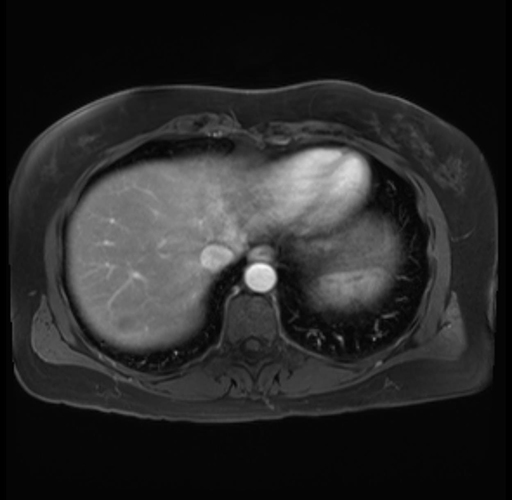

Imaging Analysis

Look through the patient's CT scan to identify any areas of concern for the necessary procedure.

Based on your CT findings, which issue(s) are present and would give reason for "planned slowing down moment(s)" in this case?

Considering a standard distal pancreatectomy procedure, what step(s) of the operation would you do differently in this case?